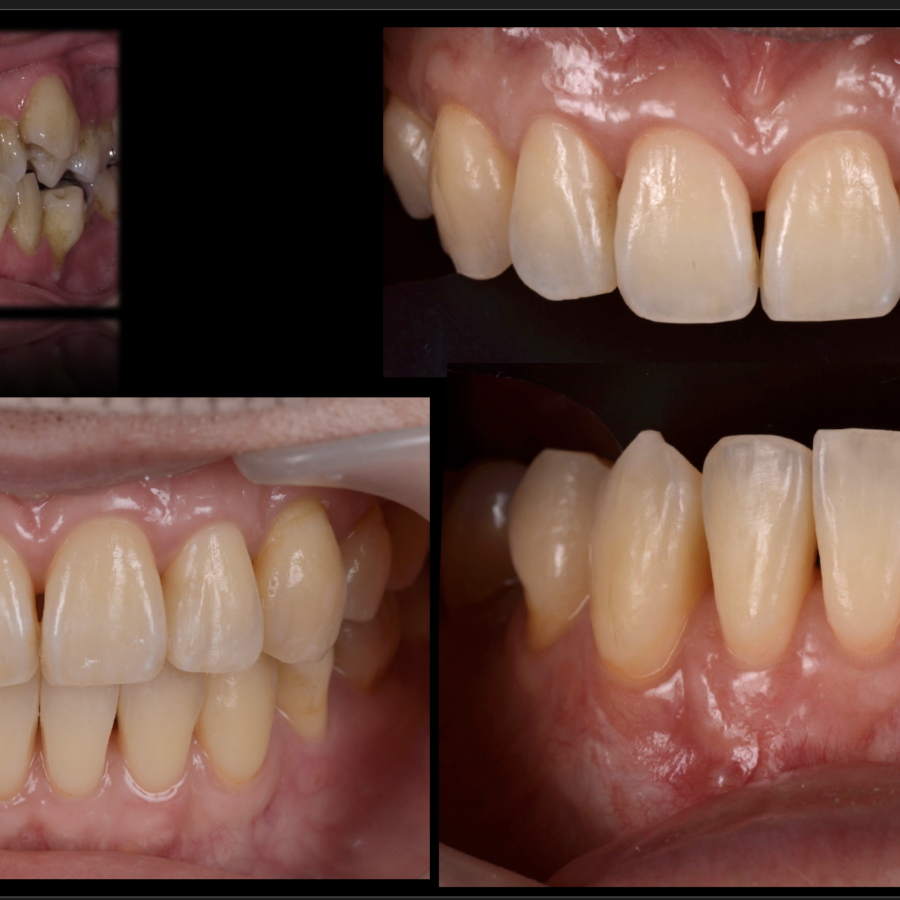

歯周再生治療

審美と健康の⻑期的な両⽴には、健全な⻭周組織と健康的な⻭並びが基本であると考え、

可能な限り天然⻭を保存し、審美と健康の⻑期的な両⽴を⽬指したエビデンス(科学的根拠)に

基づいた治療を基礎研究レベルから実際の臨床まで真剣に取り組んでおります。